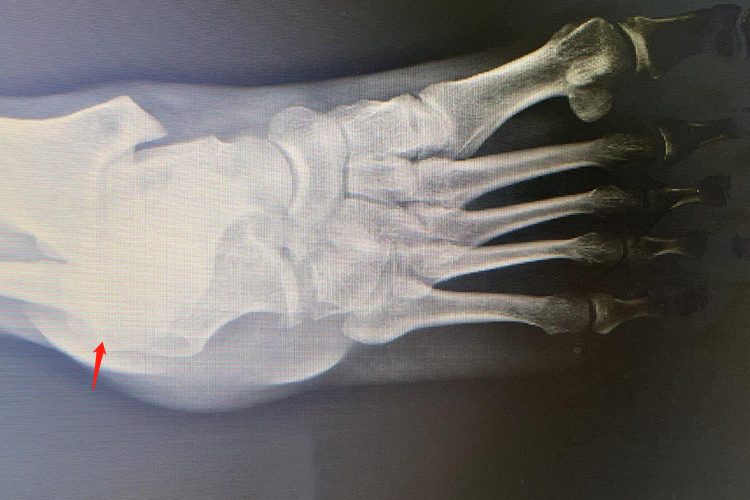

右脚骰骨骨折后可能会出现一系列后遗症,包括慢性疼痛、创伤性关节炎、足弓塌陷、骨折不愈合或延迟愈合、肌肉萎缩和力量下降等方面,若出现相关症状,应及时就医诊治。

4、骨折不愈合或延迟愈合:如骨折严重、治疗不当、患者自身健康状况不佳等,骰骨骨折可能无法正常愈合或愈合时间延长,会导致长期的疼痛、肿胀,严重影响足部功能,甚至可能需要再次手术干预。